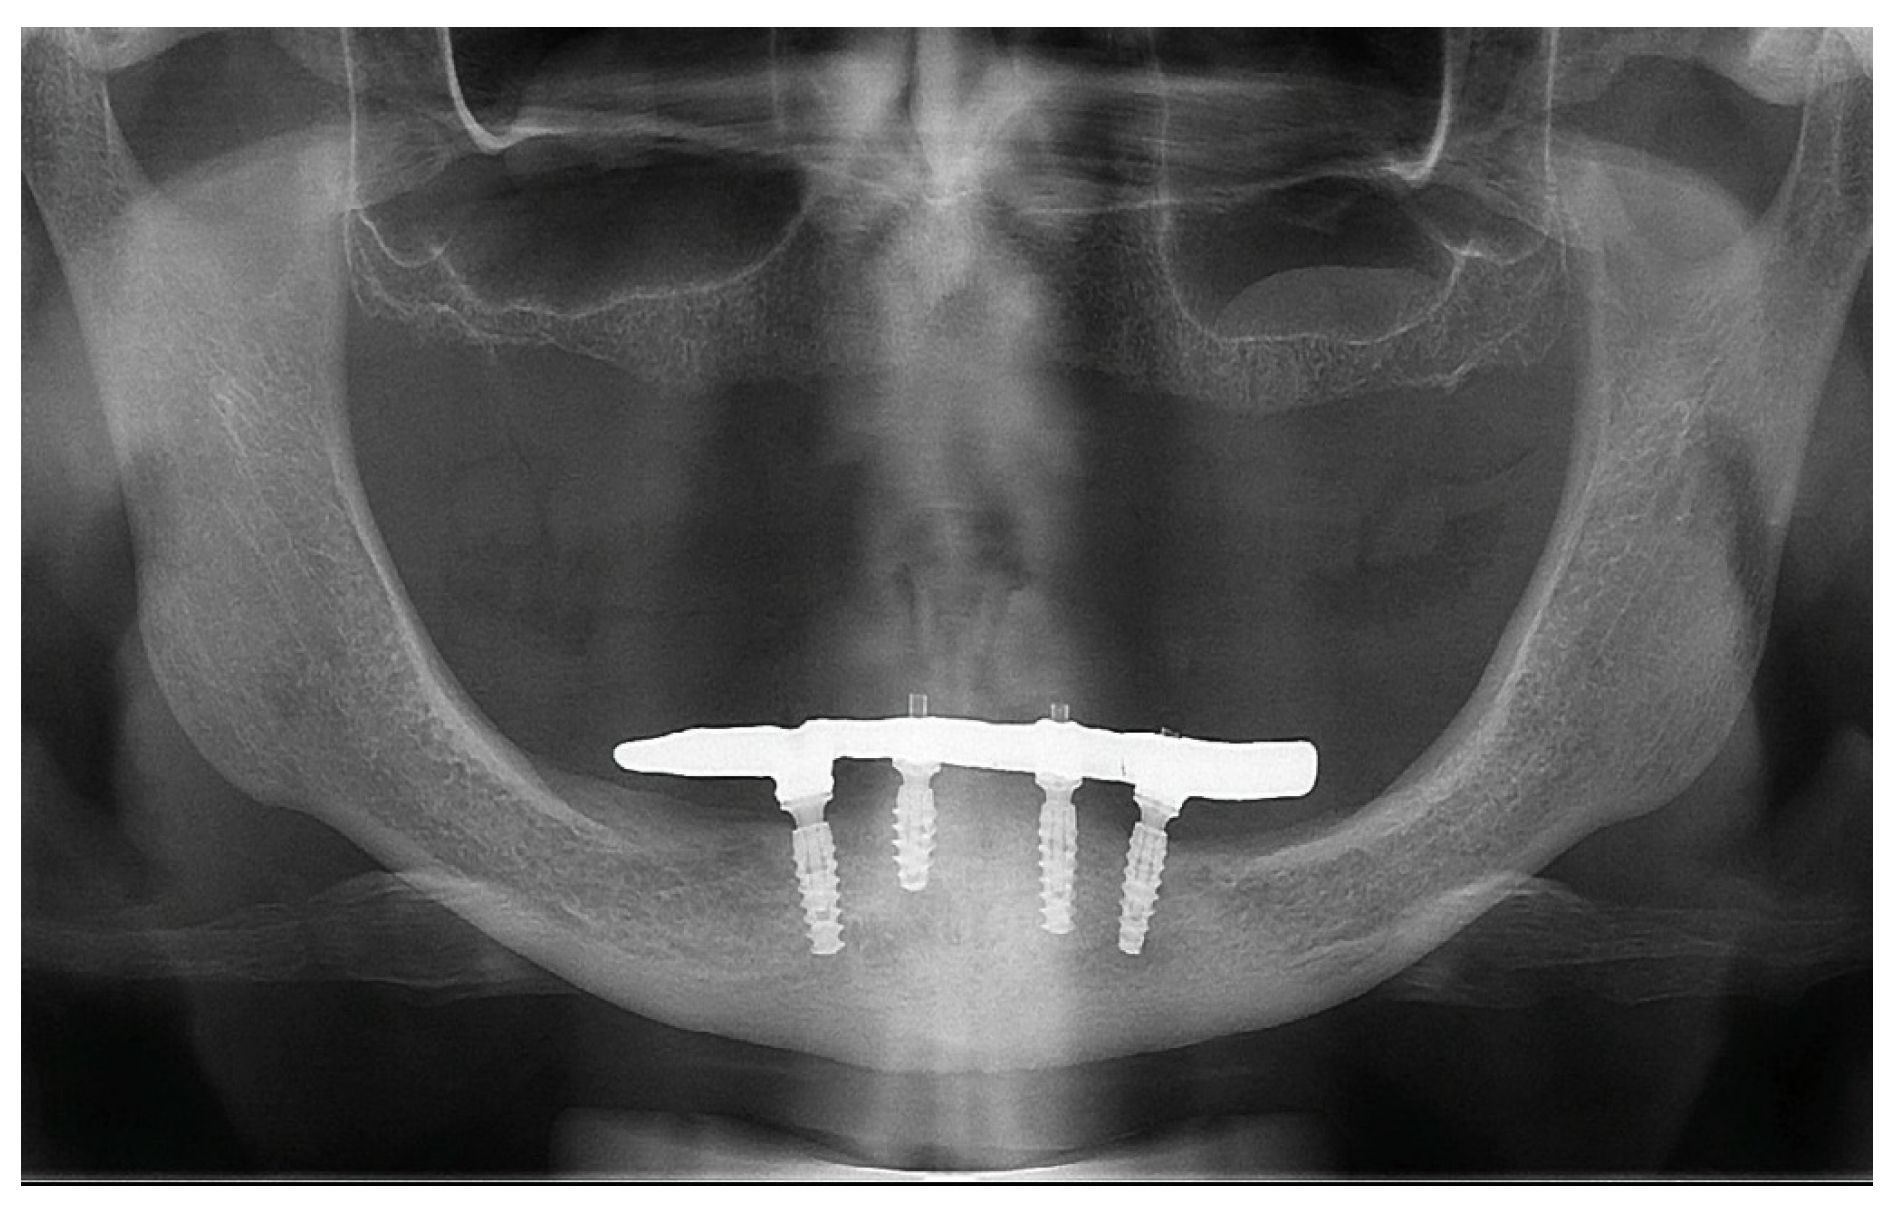

2. Case Report